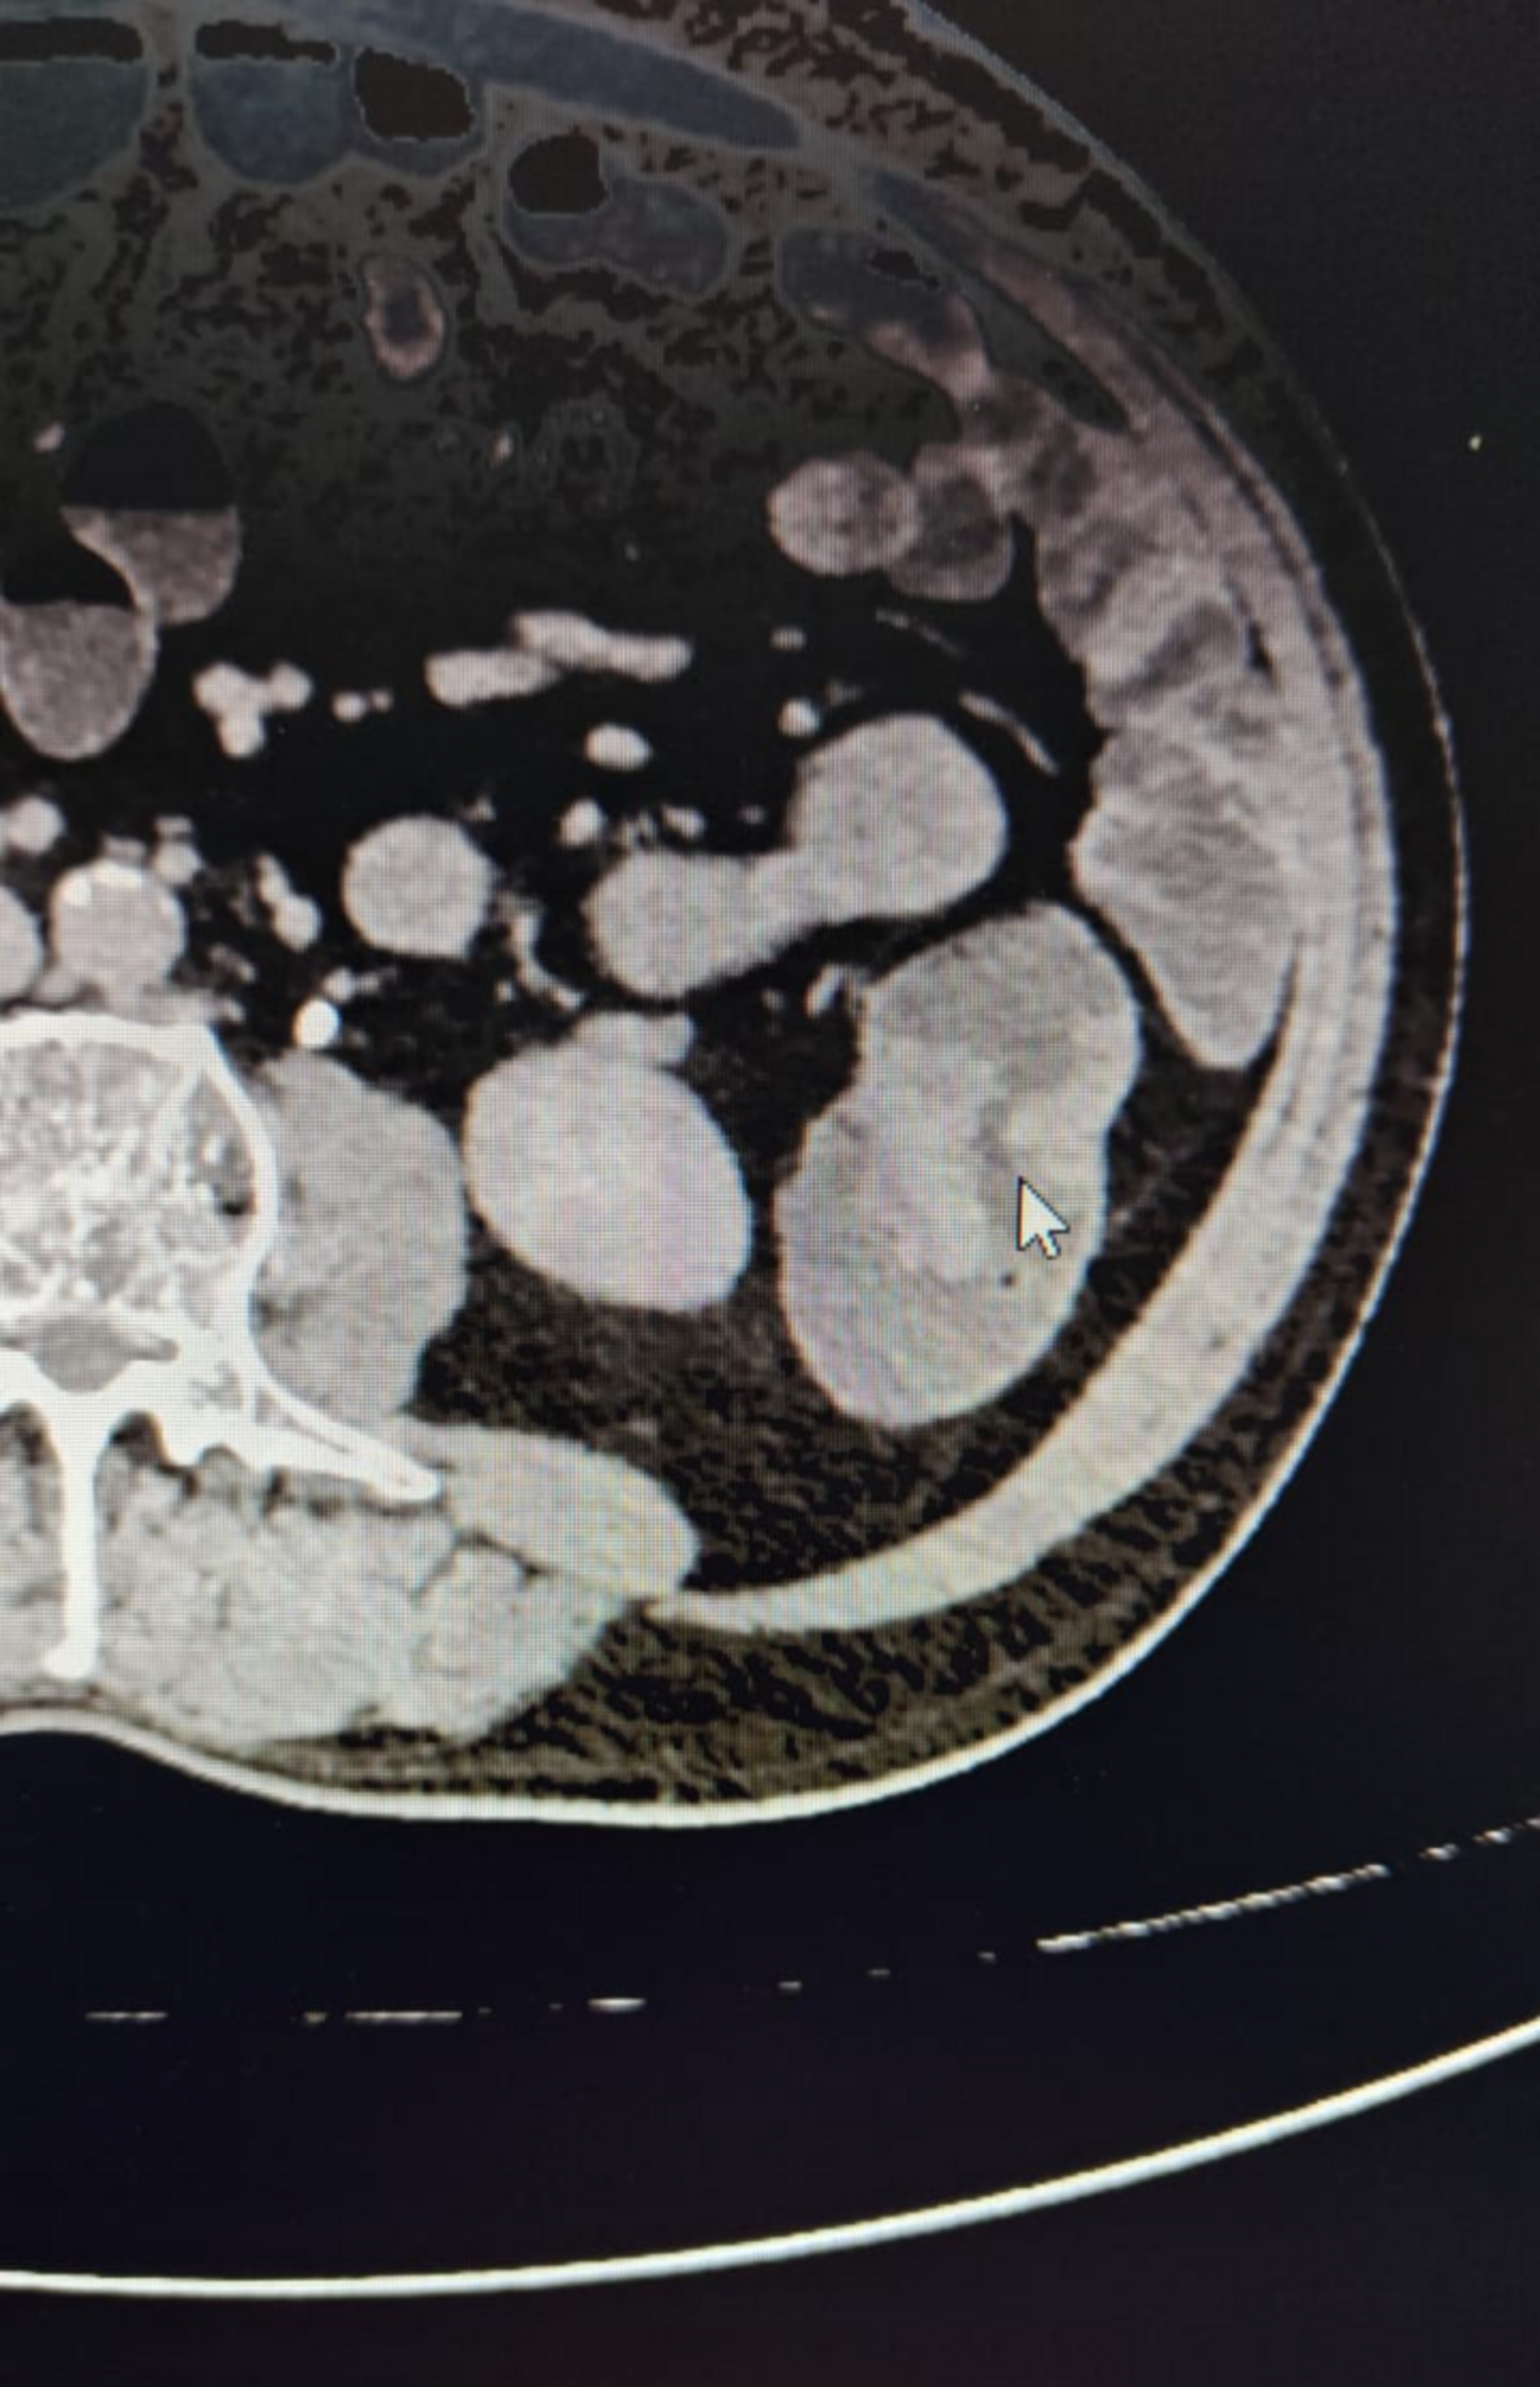

Case Summary Case Title: Small Bowel Tumor Final Diagnosis: Pseudotumor / Organized Abscess Patient Profile Age/Sex: 50-year-old male Clinical Pres...